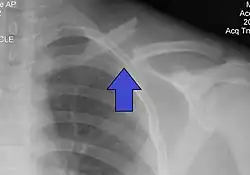

X-ray of a left clavicle fracture

Diagnostic methodBased on symptoms, confirmed with X-rays[2]

It is often caused by a fall onto a shoulder, outstretched arm, or direct trauma.[1][3] The fracture can also occur in a baby during childbirth.[1] The middle section of the clavicle is most often involved.[3] Diagnosis is typically based on symptoms and confirmed with X-rays.[2]

The basic method to check for a clavicle fracture is by an X-ray of the clavicle to determine the fracture type and extent of injury. In former times, X-rays were taken of both clavicle bones for comparison purposes. Due to the curved shape in a tilted plane X-rays are typically oriented with ~15° upwards facing tilt from the front. In more severe cases, a computerized tomography (CT) or magnetic resonance imaging (MRI) scan is taken. However, the standard method of diagnosis through ultrasound imaging performed in the emergency room may be equally accurate in children.[6]